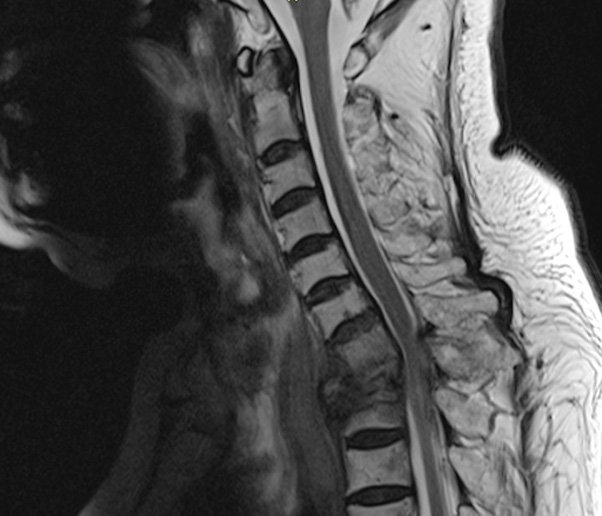

- Chụp cắt lớp vi tính (CT): CT scan để xem xét sự phát triển của khối u và xác định vị trí của chúng.

- Chụp cộng hưởng từ (MRI): MRI để xem xét sự phát triển của khối u và xác định vị trí của chúng.